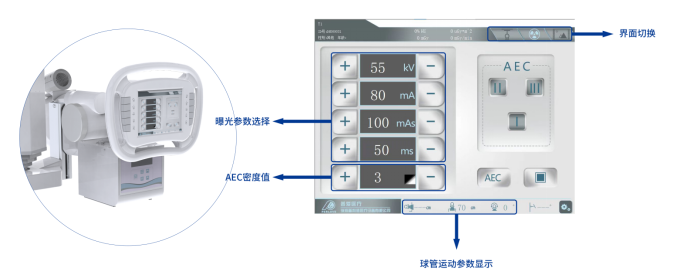

● 曝光前的预设均可近台设置

智能触控系统通过屏幕操作,可以在进行曝光工作检查前对数据进行调整。

● 信息双向传输

触控屏与工作台信息同步,支持在任意一侧登记病人信息。

● 3D摆位指示

医生选择需要拍摄的部位,自动生成摆位示意图像,引导病人快速准确的完成摆位。

● 画面自适应

屏幕配置重力感应装置,画面自动旋转调整,便于各个角度下的操作。